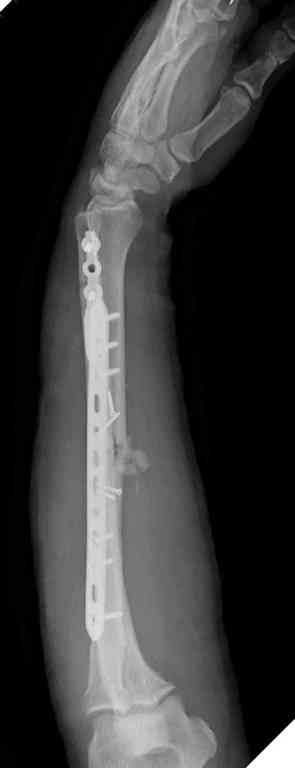

Множественная огнестрельная травма конечностей, перелом костей предплечья, фиксация в первые часы и дефект мягких тканей, мероприятия по закрытию...